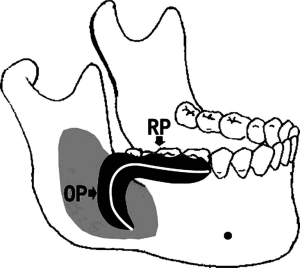

In the model group, the drainage plug completely fitted the postoperative cavity without gaps (Figure 3). One end of the drainage tube passed straight into the cyst cavity [Figure 4, obturation part (OP)], and the other end opened in the mouth lateral to the gum [Figure 4, retention part (RP)] to ensure the timely drainage of cyst effusion. With the drainage plug, the recovery time of patients was effectively shortened, and the postoperative care time was also greatly reduced.